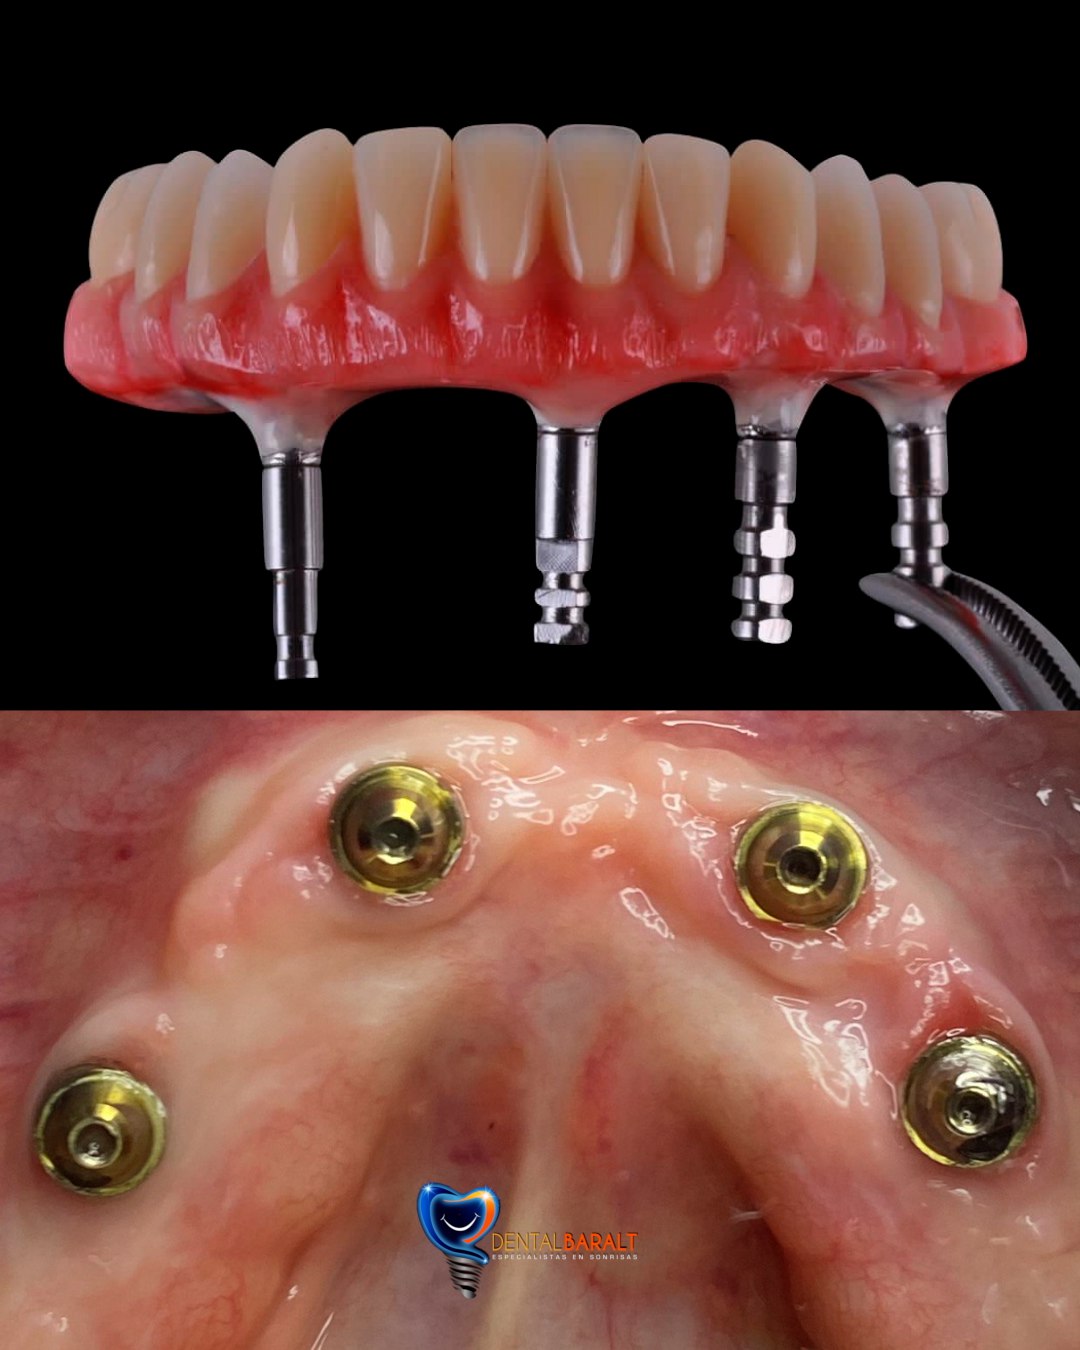

Desde prótesis parciales hasta prótesis completas, tenemos la solución ideal para recuperar tanto la funcionalidad como la estética de tu boca.

Usamos materiales resistentes y estéticos para garantizar que tu prótesis se vea y funcione como dientes naturales.

Ofrecemos prótesis dentales fijas y removibles diseñadas específicamente para ti, asegurando un ajuste perfecto y una sonrisa natural.

Prótesis dentales reemplazan dientes faltantes, pueden ser parciales o completas.

Cuando estés en presencia de ausencias dentarias, y estas pueden ser reemplazadas de distintas maneras entre ellas tenemos el grupo de las fijas y el grupo de las removibles, así como también realizamos prótesis de mayor envergadura como coronas sobre implante y prótesis hibrida.